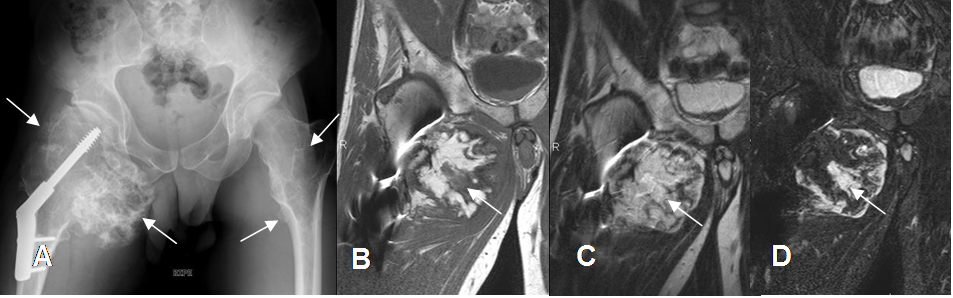

Fig 80 B. Osteocondroma malignizado.

A: Rx AP. Osteocondromatosis múltiple (Flechas) y fractura patológica en la cadera derecha, fijada con material de osteosíntesis.

B: RM coronal en T1, C: RM coronal en T2 y D: RM coronal en STIR. Lesión de aspecto condroide que ha aumentado de tamaño. En la parte central se encuentra área hipointensa en T1 e hiperintensa en T2 y STIR, que hacen sospechar la transformación a condrosarcoma.